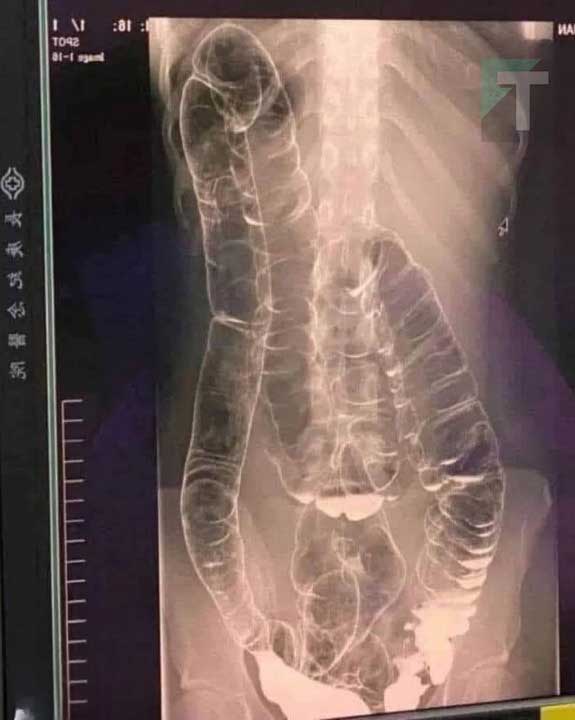

Η παρακάτω εικόνα με ακτίνες Χ ανήκει σε μια νεαρή γυναίκα που έπασχε από χρόνια δυσκοιλιότητα για χρόνια.

Μια μέρα, η κατάστασή της επιδεινώθηκε και έμεινε για πάνω από δύο εβδομάδες χωρίς κένωση.

Αναζήτησε τελικά ιατρική βοήθεια, αλλά τα αποτελέσματα ήταν ανησυχητικά.

Στην ακτινογραφία, μπορείτε να δείτε πώς το κόλον έχει επεκταθεί δραματικά, φτάνοντας μέχρι την περιοχή του θώρακα, κοντά στην καρδιά.

Οι φυσιολογικές πτυχές και διπλώσεις του παχέος εντέρου, που είναι απαραίτητες για τη λειτουργία του, έχουν σχεδόν εξαφανιστεί λόγω υπερβολικού φουσκώματος και διάτασης.